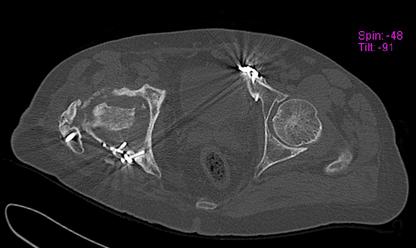

Пациент 49 лет, паровозная травма 23.2.2006, получил вертикальная нестабильное повреждение таза, разрыв левого крестцово-подвздошного сочленения, перелом лонной, седалищной костей слева, T-образный оскольчатый перелом правой вертлужной впадины с переломом заднего края, вывих правого бедра, посттравматическая пояснично-крестцовая плексопатия с обеих сторон, паралич мышц правой голени.

В день травмы - вправление вывиха, скелетное вытяжение, 14.3.2006 чрескостный остеосинтез таза. 20.4.2006 остеосинтез правой вертлужной впадины пластинами, осложнившийся нагноением межмышечной гематомы правой ягодичной области. Получал консервативное лечение, было достигнуто полное заживление раны. 24.7.2006 введены илиосакральные винты слева. С декабря 2006 года и по настоящее время ходит на костылях без опоры на правую ногу. Планируется THA. Помогите определиться с вариантом костной пластики? И какую укрепляющую конструкцию использовать?